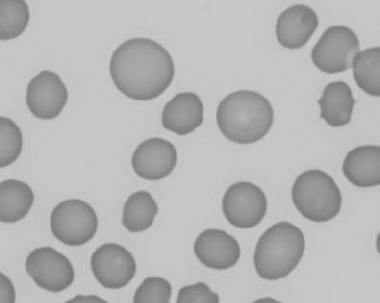

Figure 1.3 Canine blood film showing acanthocytes (also see color section).

Figure 1.4 Canine blood film showing anisocytosis (also see color section).

Figure 1.5 Bovine blood film showing basophilic stippling within a macrocyte as part of the regenerative response (also see color section).

Figure 1.6 Canine blood film showing basophilic stippling due to lead toxicosis (also see color section).

Figure 1.7 Canine blood film showing blister cells due to oxidative damage (also see color section).

Figure 1.8 Canine blood film showing codocytes. Up to 50% codocytes may be normal in a dog (also see color section).

Figure 1.9 Canine blood film showing eccentrocytes due to oxidative damage (also see color section).

Figure 1.10 Canine blood film showing echinocytes I (also see color section).

Figure 1.11 Canine blood film showing echinocytes III (also see color section).

Figure 1.12 Feline blood film showing echinoelliptocytes (also see color section).

Figure 1.13 Canine blood film showing Heinz bodies and ghost cells due to oxidative damage. There are also several polychromatophils (also see color section).

Figure 1.14 Canine blood film stained with new methylene blue, to demonstrate Heinz bodies (also see color section).

Figure 1.15 Canine blood film showing keratocytes and schizocytes (erythrocyte fragments) due to fibrin strand injury. A codocyte and a polychromatophil also appear in the field (also see color section).

Figure 1.16 Feline blood film showing Mycoplasma hemofelis organisms (hemobartonellosis). Organisms are not always visible in blood smears from infected cats (also see color section).

Figure 1.17 Canine blood film showing several macrocytes (also see color section).

Figure 1.18 Canine blood film showing a metarubricyte There is also a polychromatophilic macrocyte in the field (also see color section).

Figure 1.19 Canine blood film showing microcytic, hypochromic erythrocytes consistent with iron deficiency anemia. There are two polychromatophils in the field, indicating that the anemia is regenerative (also see color section).

Figure 1.20 Canine blood film showing two macrocytes with nuclear remnants (also see color section).

Figure 1.21 Bovine (calf) blood film showing marked poikilocytosis (normal?) (also see color section).

Figure 1.22 New methylene-blue-stained Canine blood film showing reticulocytes (also see color section).

Figure 1.23 Canine blood film showing rouleaux formation (also see color section).

Figure 1.24 Canine blood film showing spherocytosis and polychromasia due to immune-mediated hemolytic anemia (also see color section).

Figure 1.25 The red blood cell cytoskeleton.